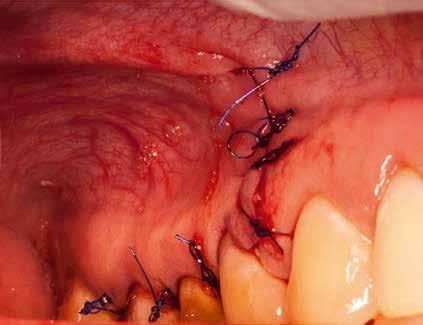

A preprotetikai fázisban el kell látnunk a diagnosztizálásra került kórfolyamatokat, megfelelő pozícióba kell állítanunk a megtartani kívánt fogakat, pótolnunk kell az elvesztett csontállományt, valamint gondoskodnunk kell az íny megfelelő állapotáról. Ha szükség van rá, úgy a foghiányok pótlására szolgáló dentális implantátumok is ebben a fázisban kerülnek behelyezésre. Általánosságban elmondható, hogy azokat a kezeléseket, amelyek befejezése biológiai okok miatt hosszú időt vesz igénybe (pl.: fogszabályozás, csontpótlás, implantáció), a lehető leghamarabb érdemes elkezdeni.